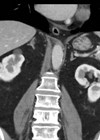

Renal masses

Case 1 A 70-year-old female presented under the medical team with malaise, weight loss, and deranged liver function tests (LFTs) and calcium (ALP 350, GGT 650, Serum bilirubin 29, normal aminotransferases, Ca 3.3). An abdominal ultrasound scan (USS) was performed...